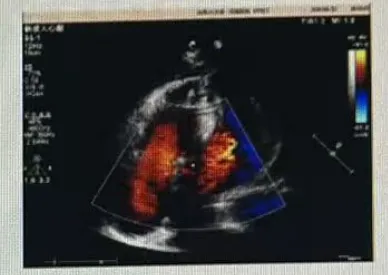

超声所见:各房室腔内径正常范围,室间隔及左室壁增厚,运动协调,收缩幅度正常。各膜形态、结构、运动未见异常。升主动脉增宽,余大动脉关系、内径正常。心包腔未见异常。

检查提示:升主动脉增宽;室间隔及左室壁增厚;主动脉瓣大量反流、二尖瓣反流(均少量);主动脉瓣狭窄(重度)。

术后超声提示,置换瓣功能正常,三尖瓣反流(少量),心包积液(少量)。

术后超声